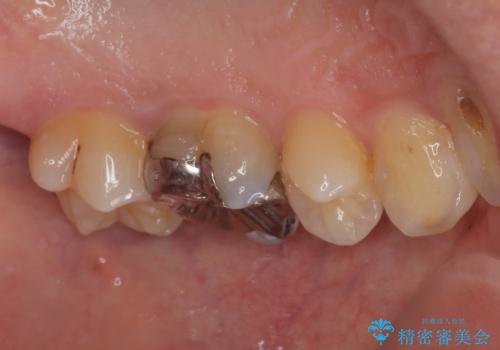

- 銀歯を外したいとのことで来院された患者様です。検査の結果、メタルインレーの範囲も大きいためオールセラミッククラウンにて補綴治療を行っていくことにしました。

拡大鏡視野下でメタルインレー、虫歯の除去を行いオールセラミッククラウンに適した形に整えました。

歯と歯茎の間に圧排糸と言われる糸を入れてシリコーン印象材にて型どりをしました。